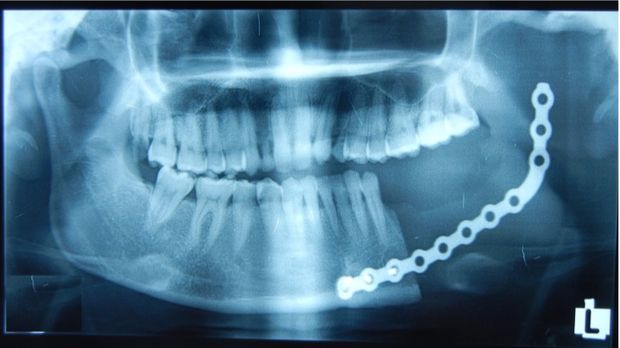

Rahang pasca rekonstruksi (Foto: drg Dhanni Gustiana SpBMM) |

Rahang pasca rekonstruksi (Foto: drg Dhanni Gustiana SpBMM)